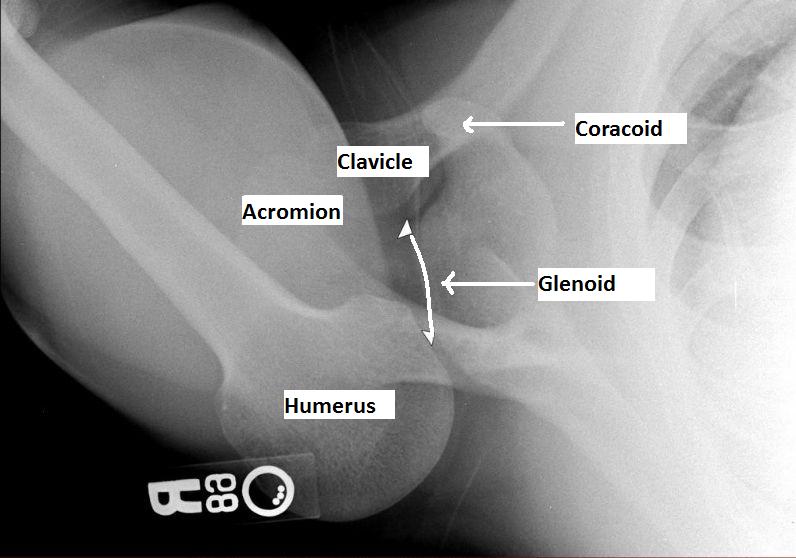

Posterior Shoulder Dislocation On X-Ray . The shoulder girdle is a complex articulation. Left shoulder pain after pushing a heavy object. diagnosis is made radiographically in the setting of acute dislocations. The term shoulder dislocation refers to the complete displacement of the humeral head from the glenoid fossa, while shoulder subluxation refers to the partial displacement of the. The shoulder is rotated such that the. posterior shoulder dislocation. posterior shoulder dislocation. Chronic instability can be diagnosed with presence of positive. posterior shoulder dislocation is both significantly less common and significantly harder to spot than anterior dislocation. There is lack of overlap between the glenoid and the humeral head. Sex distribution is bimodal and relative incidence is.

The term shoulder dislocation refers to the complete displacement of the humeral head from the glenoid fossa, while shoulder subluxation refers to the partial displacement of the. posterior shoulder dislocation. diagnosis is made radiographically in the setting of acute dislocations. Left shoulder pain after pushing a heavy object. Chronic instability can be diagnosed with presence of positive. The shoulder is rotated such that the. posterior shoulder dislocation. There is lack of overlap between the glenoid and the humeral head. Sex distribution is bimodal and relative incidence is. The shoulder girdle is a complex articulation.

Posterior Shoulder Dislocation On X-Ray posterior shoulder dislocation is both significantly less common and significantly harder to spot than anterior dislocation. Left shoulder pain after pushing a heavy object. The term shoulder dislocation refers to the complete displacement of the humeral head from the glenoid fossa, while shoulder subluxation refers to the partial displacement of the. There is lack of overlap between the glenoid and the humeral head. posterior shoulder dislocation. posterior shoulder dislocation is both significantly less common and significantly harder to spot than anterior dislocation. diagnosis is made radiographically in the setting of acute dislocations. posterior shoulder dislocation. The shoulder girdle is a complex articulation. Sex distribution is bimodal and relative incidence is. The shoulder is rotated such that the. Chronic instability can be diagnosed with presence of positive.